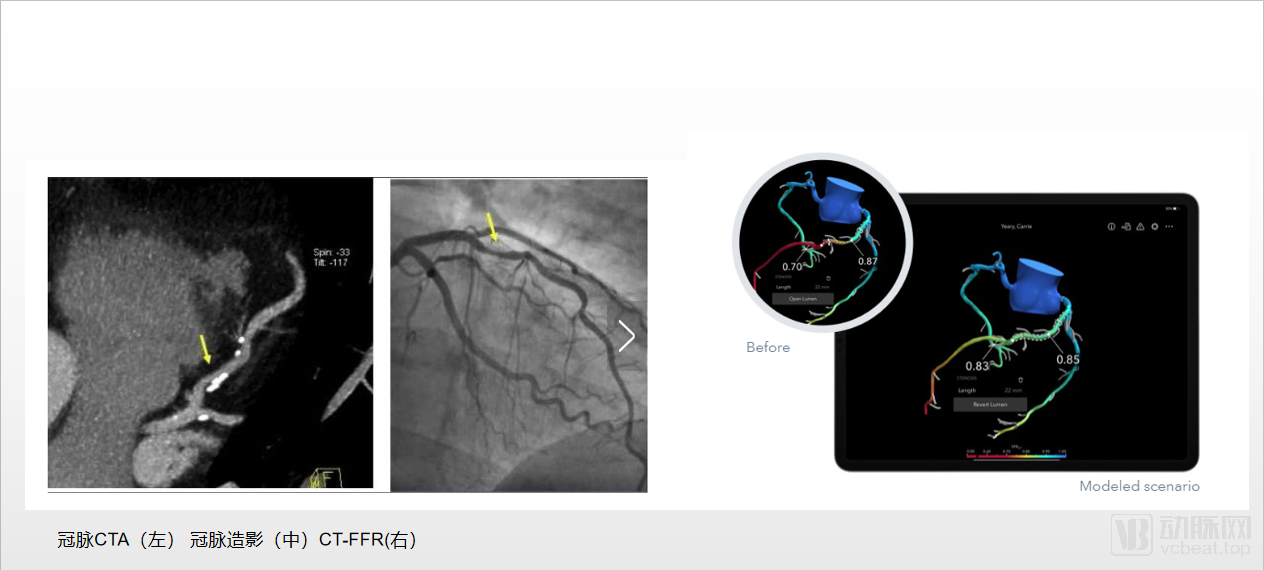

国内超10家企业扎根影像FFR领域,国外诞生独角兽,国内如何... 推荐

来源:动脉网作者:杨雪心脏曾经被认为是手术的禁区,它是现代外科领域内最晚被打开的器官。作为人体的发动机,心脏不停地跳动和充沛的血液曾让外科医生无法打开心脏做手术。 著名的奥利地外科医生西奥多 ......